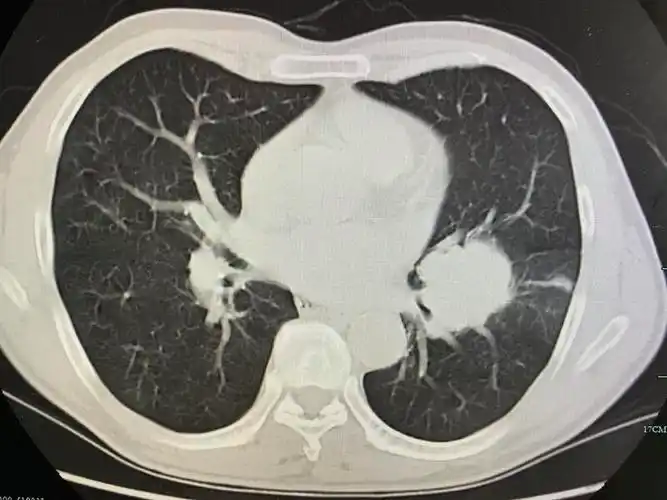

中央型肺癌ct

简述中央型肺癌特点及影像表现

中央型肺癌肺内多发转移一例!